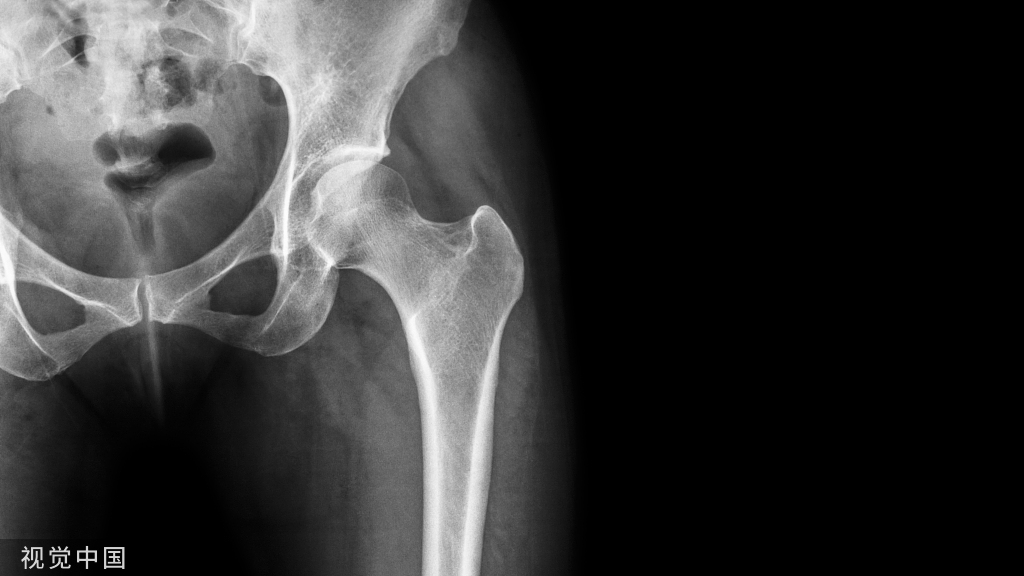

膝关节穿刺术常用于检查关节腔内积液的性质,或抽液后向关节腔内注药。膝关节腔内积液,需行关节穿刺抽液检查或引流,或注射药物进行治疗。关节腔内注射空气或造影剂,行关节造影术,以了解关节软骨或骨端的变化。

1、以髌骨中心点,作水平线和垂直线,其第一和第二象限,各做45度的平分角,该平分线与髌骨内外缘的交点,即是进针点。

2、患者仰卧位,膝关节伸直,髌骨上缘与髌骨内外侧缘的交点为两点,斜向髌股关节中心,以45°角穿刺。

3、膝关节微屈30°左右,从髌骨下方的髌韧带内侧或外侧关节间隙垂直进针。

髌骨外上缘穿刺法

定位:髌骨外上缘处与股外侧肌交界处。按压股外侧肌下凹陷处,贴指甲刺入0.5-1cm,有落空感即可。

髌骨外下缘(外侧膝眼)穿刺法

定位:屈膝90°位,髌骨下缘、髌韧带外侧1cm处(外侧膝眼,可看到一小凹陷)。

方法:用指甲定位好后,消毒患处,针头与胫骨平台平行,向内呈45度角,穿刺进入,针头完全刺入即可。

如何选择?髌骨外下缘or髌骨外上缘

(1)对于关节内有大量积液的病人,采用髌骨外上缘进针抽液,然后顺便注射玻璃酸钠。因为关节内有大量积液的时候,积液大多在髌上囊,髌股关节间隙也比较大,髌骨外上缘进针很容易操作,也可抽出积液。而对于没有关节积液的病人,髌骨外上缘进针不太容易操作。

(2)对于没有关节积液的病人,采用髌骨外下缘(外侧膝眼)穿刺法,一定要定好位置(屈膝90度位,髌骨下缘、髌韧带外侧1cm处),采用8号针头,与胫骨平台平行,向内呈45度角,针头完全刺入,有一种落空感,有时回抽会抽出关节液,此时可放心注射;回抽如没抽出关节液,可以注射玻璃酸钠,如果注射时比较轻松,那就没有问题,如果注射时比较费力,病人感觉痛、胀,可以进一步向里面插下针头,左右移动下,注射时比较轻松病人无不适即可再注射。只要熟练操作,定位正确,及时调整,病人很少出现注射后不适的。